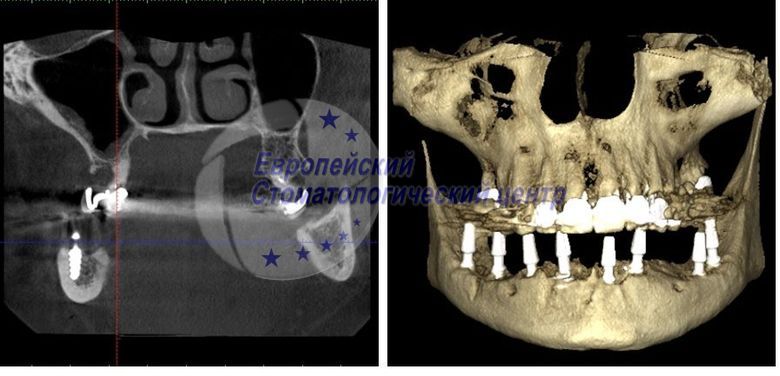

КТ через рік після операції

КТ після операції імплантати стоять поруч з нижньощелепним каналом 2

КТ через рік після операції. Абсолютна стабільність кісткової тканини біля інмплантатов